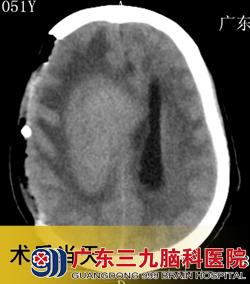

入院3天后,潘女士在广东三九脑科医院接受了“右侧基底节占位性病变取病理活检术+去骨瓣减压术”,术后病理结果为:弥漫大B细胞淋巴瘤。术后第4天,予以抢救性全脑放疗,并同步化疗。2012年11月4日复查头颅CT见右侧基底节病灶明显缩小,中线回位,遂继续予以全脑及局部残留肿瘤放疗。www.999brain.com